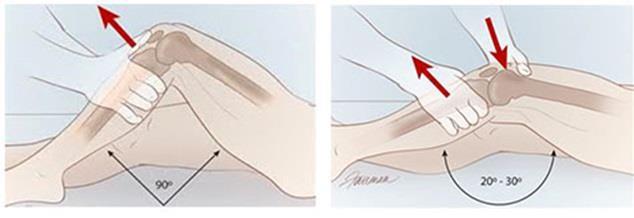

Tanı nasıl Konur?

Muayene: Akut yırtıklarda hasta dizinde şişlik ile gelir, diz ileri derece ağrılı ve gergindir, ağrı nedeni ile bazen spesifik muayene testlerini yapmak mümkün olmayabilir.

Kronik dönemde gelen hastaya detaylı diz muayenesi yapılır, bu esnada ön çapraz bağ yırtığı için spesifik testlerde(Lachman testi, Ön Çekmece testi, pivot-shift testi vb.) uygulanır. Detaylı bir fizik muayene ile %90 tanı konulur. Bazen hasta ağrı duyma endişesi nedeni ile kaslarını kasarak net muayene sonucu elde edilmesini önler, ameliyat öncesinde anestezi altında muayene yapılması tanı değerini yükseltir.

Tanı nasıl Konur?

Muayene: Akut yırtıklarda hasta dizinde şişlik ile gelir, diz ileri derece ağrılı ve gergindir, ağrı nedeni ile bazen spesifik muayene testlerini yapmak mümkün olmayabilir.

Kronik dönemde gelen hastaya detaylı diz muayenesi yapılır, bu esnada ön çapraz bağ yırtığı için spesifik testlerde(Lachman testi, Ön Çekmece testi, pivot-shift testi vb.) uygulanır. Detaylı bir fizik muayene ile %90 tanı konulur. Bazen hasta ağrı duyma endişesi nedeni ile kaslarını kasarak net muayene sonucu elde edilmesini önler, ameliyat öncesinde anestezi altında muayene yapılması tanı değerini yükseltir.